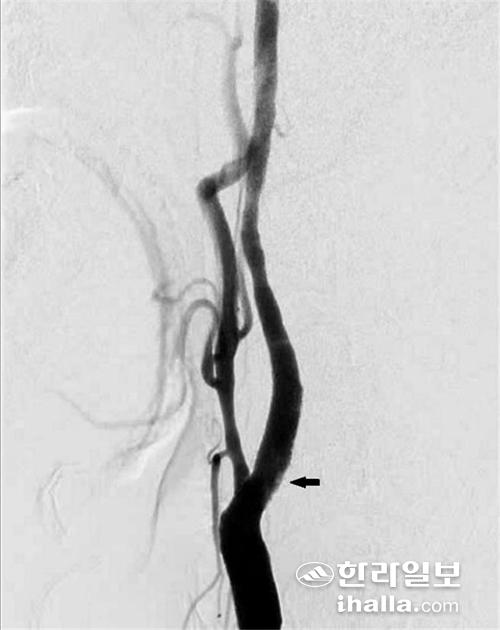

경동맥 협착증의 진단을 위한 비침습적인 검사로는 경동맥 초음파 및 CT, MRI를 이용한 혈관조영술이 있고, 침습적인 검사로는 뇌혈관 조영술 (transfemoral cerebral angiography)이 있다. 이 중 뇌혈관 조영술은 경동맥 협착증의 진단에 있어 가장 정확한 검사 중 하나로, 경동맥 재개통을 고려하는 환자들에게 널리 행해지고 있다.

경동맥 스텐트 삽입술은 대퇴동맥으로 관을 삽입해 경동맥 협착증이 있는 부위에 스텐트라는 금속 그물망을 펼쳐 좁아진 혈관을 넓혀주는 방법이다. 예전에는 경동맥 스텐트 삽입술이 주로 전신마취 하에 수술하기가 위험한 환자 및 경동맥 협착 부위가 너무 머리 쪽으로 높게 위치하고 있어 경동맥 내막절제술을 받기 힘든 환자들에게 선택적으로 행해졌다.